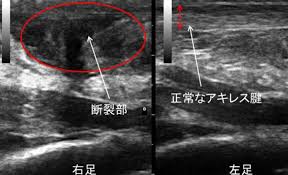

アキレス腱 名前アキレス腱 のアキレス腱 由来アキレス腱 アキレス腱(あきれすけん)とは?場所・位置や英語などを人体解剖図で解説アキレス腱 -アキレス腱 teamLabBodyアキレス腱 アキレス腱断裂(損傷)アキレス腱 |アキレス腱 宇都宮のはせがわ整形外科アキレス腱 簡単に巻ける!アキレス腱炎のテーピングアキレス腱 |アキレス腱 二日市の杏鍼灸整骨院アキレス腱 アキレス腱の名前の由来は?アキレス腱 |アキレス腱 ただ痩せるだけ?スッキリボディになりませんか?アキレス腱 (麻布十番)アキレス腱 症例報告アキレス腱 |